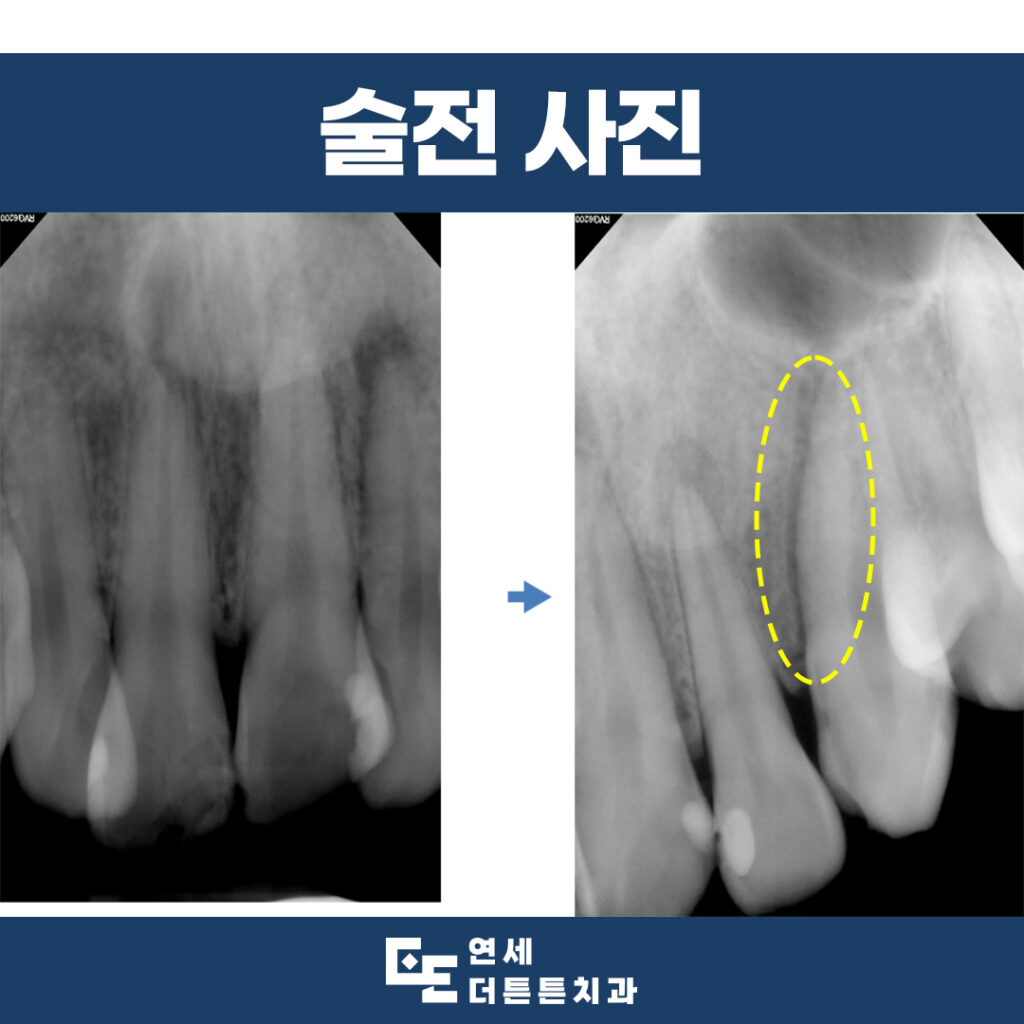

내원 당시 구내 사진과

x-ray 사진을 통해 진단해 본 결과,

가장 오른쪽의 앞니는 뿌리까지 부러져

있음을 확인할 수 있었으므로

발치를 결정할 수밖에 없었는데요.

옆여 있는 치아들도 충격을 받아

신경치료가 필요한 부위는 진행을

하기로 하였습니다.

전반적으로 6개의 앞니 모두

예후가 좋지 않음을 고려하여

장기적으로 계획을 수립하였습니다.